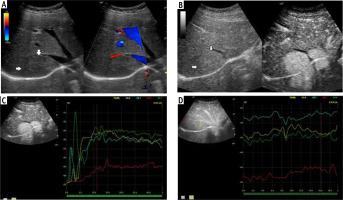

Fig. 3

Assessment of the degrees of enhancement in the post-contrast examination (CEUS). Areas of interest were placed within the lesion (depending on the size of the lesion and the uniformity of the enhancement – one or two areas – G). Another area was placed in the parenchyma of the liver – W, and in the lumen of a large vessel (most often vessels of the portal circulation – N). Enhancement curves were recorded in about 2-3 min in sequences of about 20-30 s. Values burdened with motor artifacts causing the dislocation of areas of interest were eliminated

Fig. 5

A) Image of ultrasound and color Doppler in the transverse plane, focal lesion in the right lobe of the liver identified in MRI as HCA (full white arrows). Echogenicity of the lesion is slightly higher in relation to the liver parenchyma. B) Image of CEUS in the transverse plane of the lesion identified in MRI as HCA (full white arrows). Enhancement in the early phase is higher in relation to the liver parenchyma. C) Image of CEUS. Curves of enhancement in early phase of examination. The tumor area – yellow and blue lines, enhancement appears in the hepatic veins with slight delay – the green line. Weaker and delayed enhancements in the liver parenchyma – the red line. Disturbance of the curves in the early phase of the study (0-5 s) is caused by displacement of the liver due to breathing. D) Image of CEUS. Curves of enhancement in the areas of interest in the late phase of the study are aligned. The tumor area – blue and yellow line, the hepatic vein is slightly more intensively enhanced – blue line. Slightly weaker enhancement of the liver parenchyma – the red line

Fig. 6

A) Image of ultrasound and color Doppler in the transverse plane, focal lesion in the right lobe of the liver identified in MRI as FNH (full white arrows). Echogenicity of the lesion is slightly higher in relation to the liver parenchyma. In the central part, a small scar (an empty white arrow) is more clearly visible in the color Doppler option. B) Image of CEUS in the transverse plane of the lesion identified in MR as FNH (full white arrows). Enhancement in the early phase is higher in relation to the liver parenchyma. In the central part, the area containing the vessels, corresponding to the central fibrous scar. C) Image of CEUS. Enhancement curves in the early phase of examination. The tumor area – yellow and blue lines, with slightly delayed enhancement appears in the portal system – red line. Weaker and delayed enhancement of the liver parenchyma – the green line. D) Image of CEUS. Curves of enhancement in late phase of examination align. Area of tumor – blue and red lines, slightly stronger enhancement portal vein – yellow line. Slightly weaker enhancement of the liver parenchyma – the green line